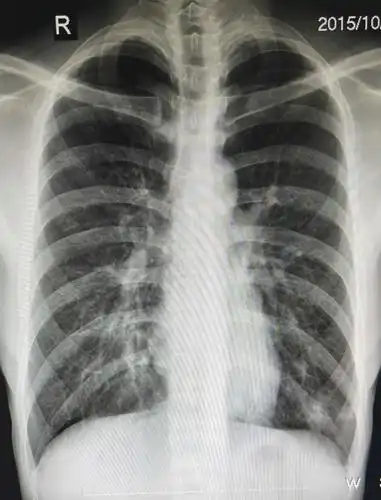

支气管炎改变这个词往往都是在影像学报告上所说的,就是说从胸片